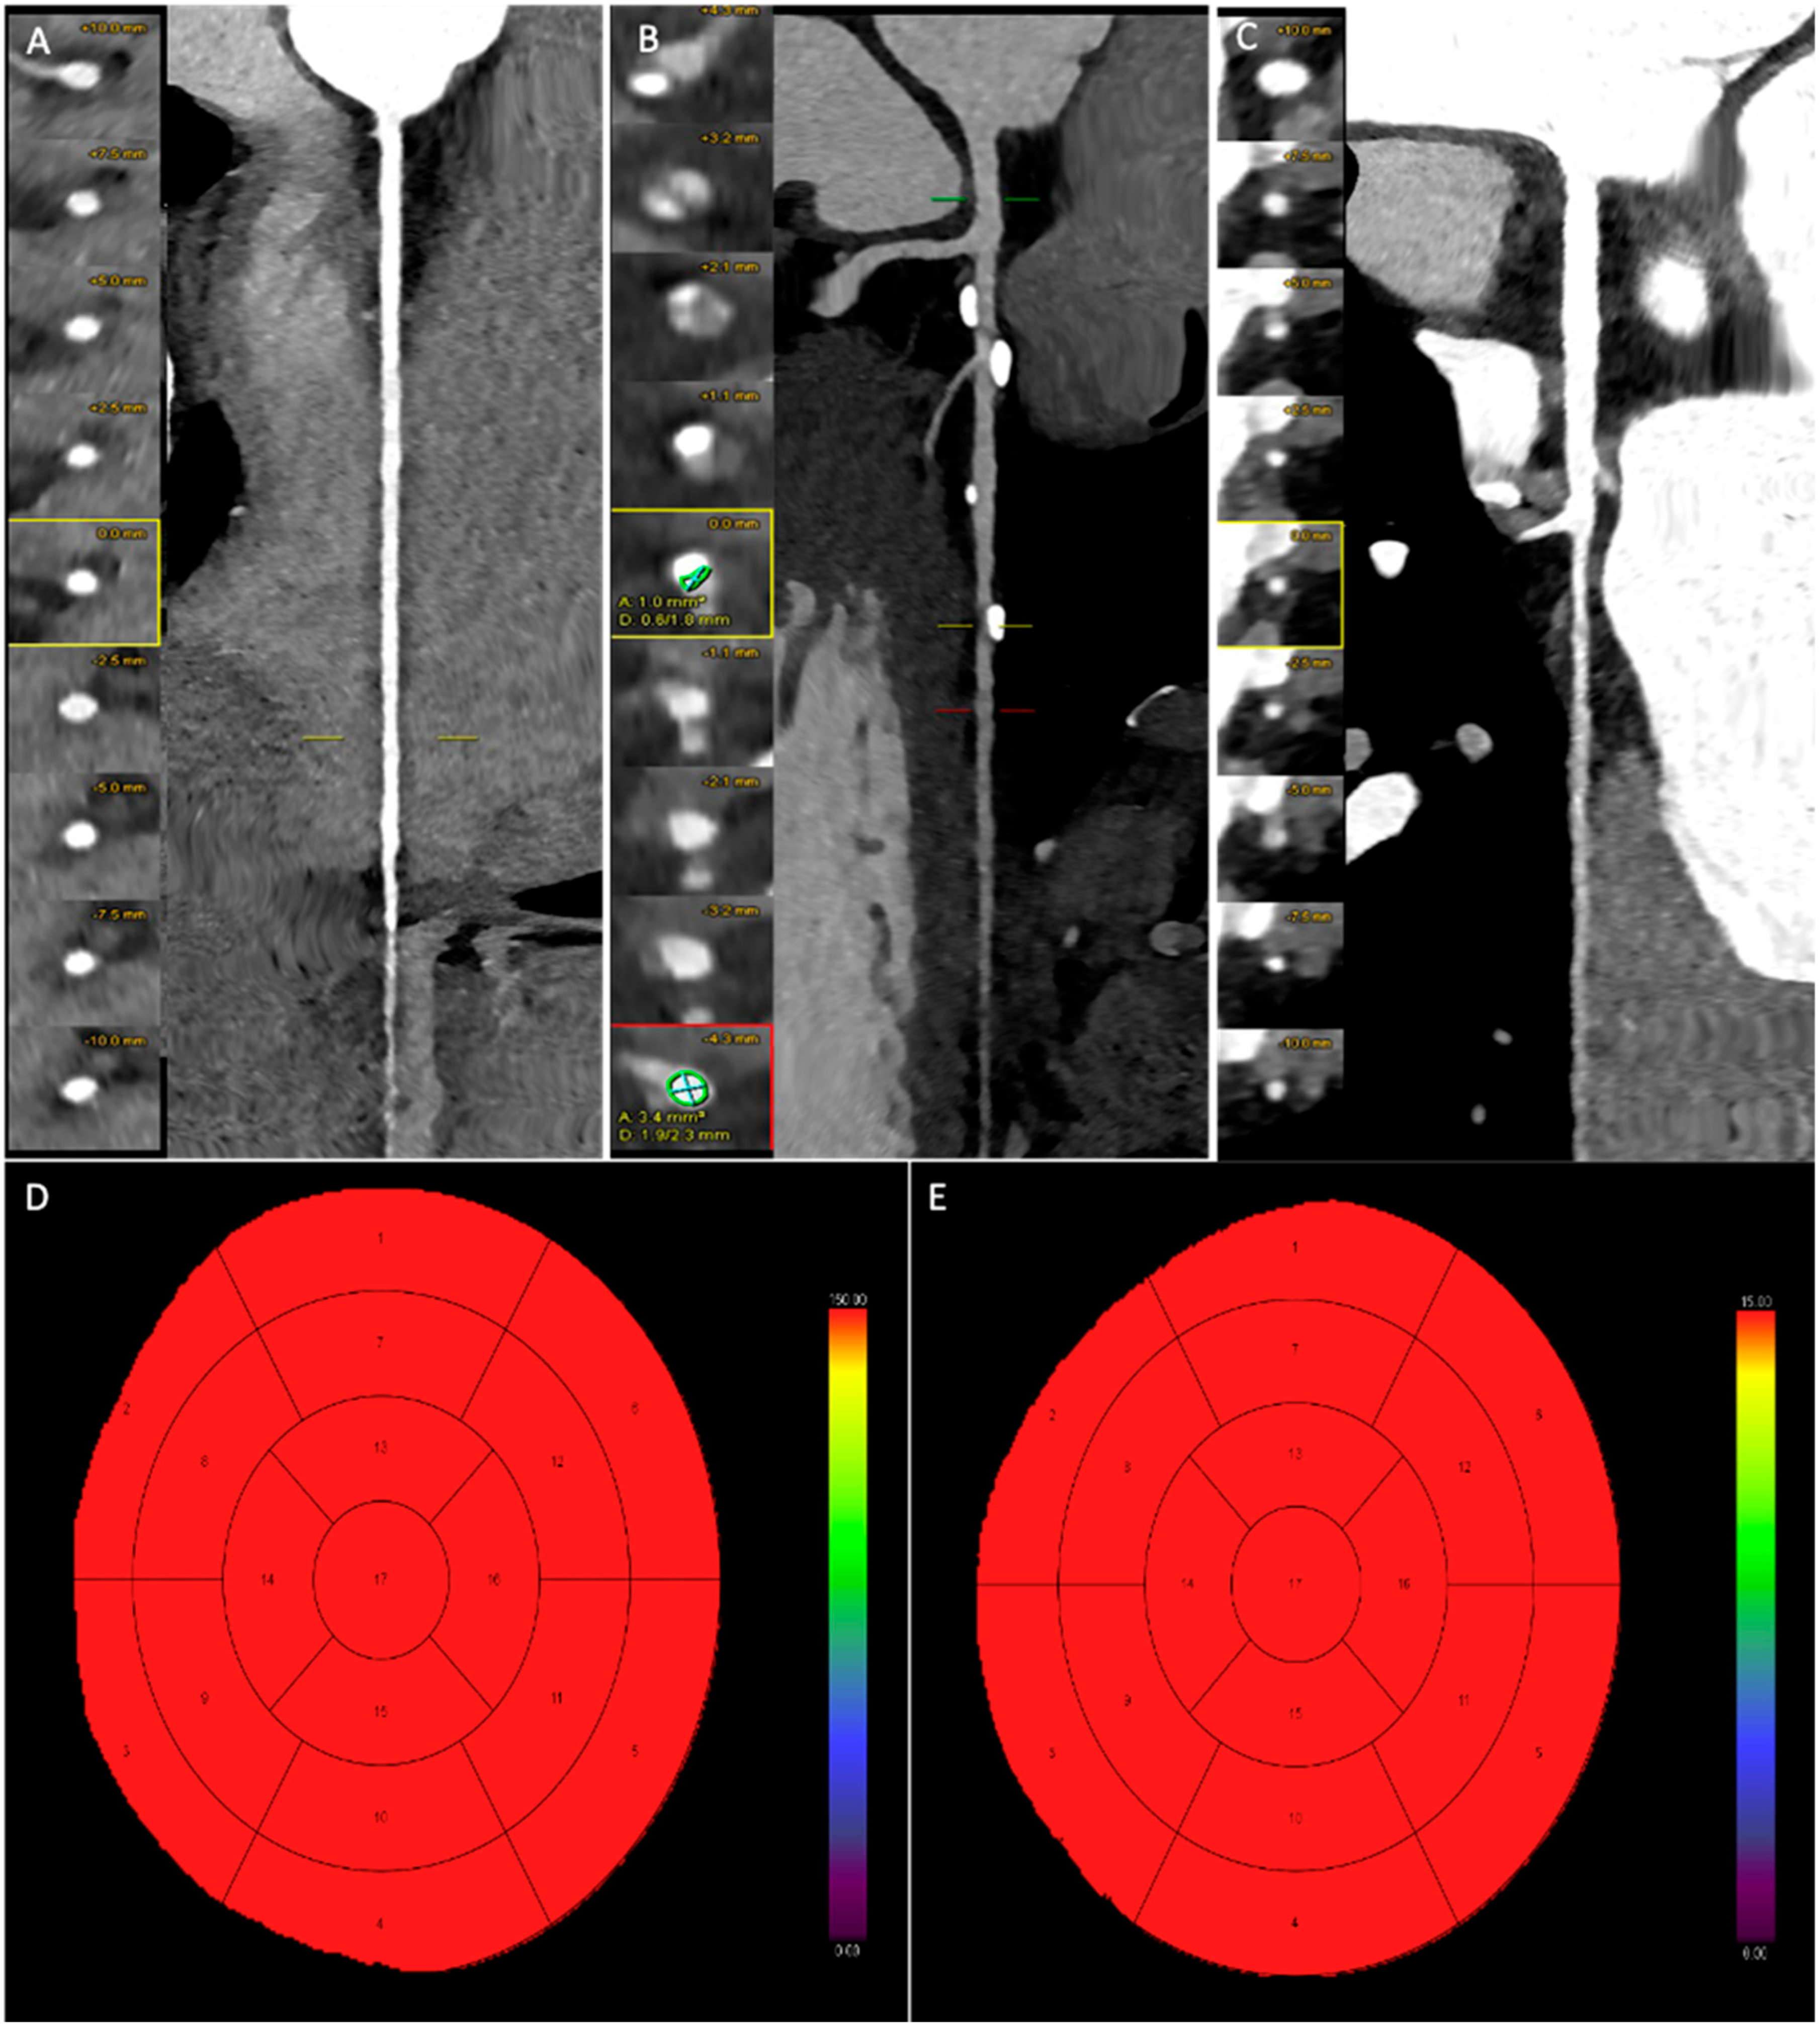

Figure 3 and Figure 4 present representative cases from our study. Figure 2 depicts a patient with moderate coronary artery stenosis without evidence of myocardial hypoperfusion, whereas Figure 3 illustrates a patient with moderate stenosis associated with stress-induced myocardial hypoperfusion.

Figure 3.

Male patient, 46 years old, with atypical chest pain and ECG abnormalities. Coronary CT angiography examination shows a regularly perfused right coronary artery without significant stenosis (A). The left anterior descending artery exhibits multiple mild stenoses (below 40%) at the mid-proximal segment, while a single moderate stenosis (50–69%) is present at the distal segment (B). The circumflex artery is regularly perfused without significant stenosis (C). (D,E) Myocardial blood flow (MBF) and myocardial blood volume (MBV) after dynamic stress CT examination, without any reductions in blood flow and volume.